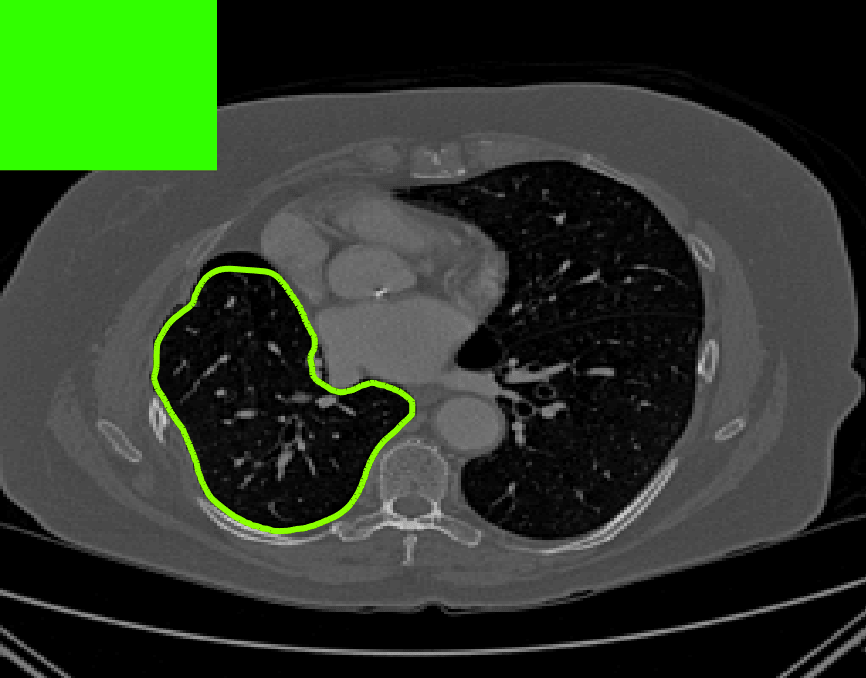

Test Images. We will perform initial tests on the images shown in Figs. 5–7. We have provided the ground truth and initialisation used for each image. Test Images 1–3 are synthetic, Test Image 4 is an MRI scan of a knee, Test Images 5–6 are abdominal CT scans, and Test Images 7–9 are lung CT scans. They have been selected to present challenges relevant to the discussion in §2. We focus on medical images as this is the application of most interest to our work. In the following we will discuss the results in terms of synthetic images (1–3) and real images (4–9). We also test the proposed approach on a larger data set of 30 CT images (a sample of which is presented in Fig. 18), comparing against existing selective methods detailed in §3.

Real Images. In Fig 12 we present results for Test Images 4–6. Here, the proposed model performs in a similar way to its competitors because these images are more typical selective segmentation problems in the sense that there is a clear distinction between the foreground and background intensities. In particular, the values in each case are: Test Image 4 , Test Image 5 , and Test Image 6 . It can be seen that the proposed model is competitive compared to previous approaches. The performance is quite poor for Test Image 5, but is arguably still the best for this challenging case. In Fig. 13 we present results for Test Images 7–9. Here the proposed model outperforms previous approaches significantly for each image. This is mainly due to the type of image considered. Specifically, the true intensities are: Test Image 7 , Test Image 8 , and Test Image 9 . The proposed model is capable of achieving results where , with other models failing completely in these cases.